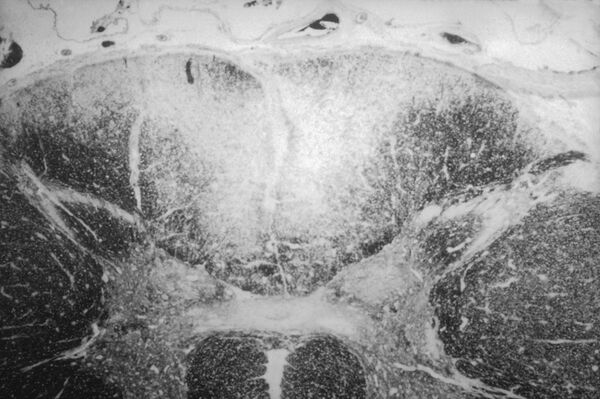

Спинная сухотка (лат. tabes dorsalis) — форма позднего нейросифилиса. Характеризуется поражением спинальных нервных корешков и задних столбов спинного мозга. Возникает обычно через 5—10 лет, изредка через 15—20 лет после инфекции сифилисом[3].

При спинной сухотке наблюдается атрофия задних корешков в зоне их вхождения в спинной мозг и задних канатиков спинного мозга. Мягкая оболочка спинного мозга мутная и утолщённая. Микроскопически наблюдаются дегенеративные изменения в задних рогах спинного мозга, в задних корешках, в проводящих путях Голля и Бурдаха, в основном в задней поверхности наблюдаются воспалительные изменения мягкой оболочки спинного мозга[2]:21.